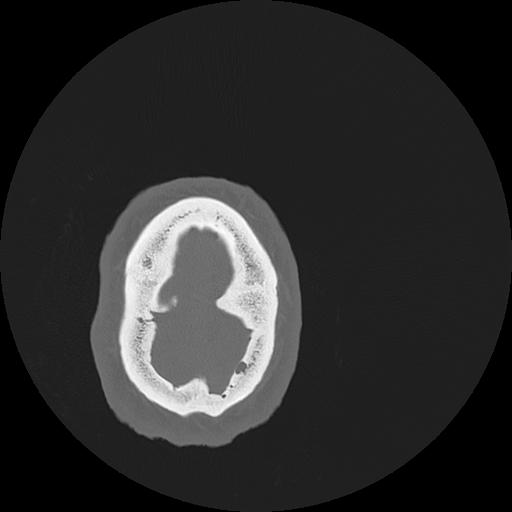

7 HUESO,,Vol,0.5,HUESO,,